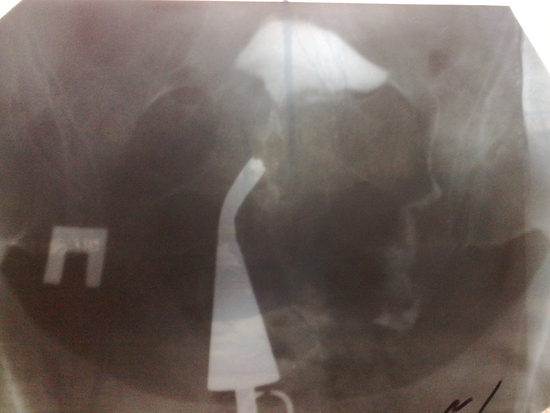

Приветик, миленькие девчоночки!!! Не знаю с чего начать, в голове дурдом. Сегодня сделали ГСГ. Результат такой, хтоя я и плохо поняла что мне бормотала Г.: показала снимки, потом сказала - "ж...па". Предложила лечить а потом на лапару, затем три месяца жить полным ходом. Если без результата - то ЭКО. Пришла я домой вся в подвешенном состоянии, немного отошла, взяла снимки и сама посмотрела. Картина такая - левой трубы я неувидела вообще, а правая есть и даже из нее вытекающая жидкость, но я то не врач и не понимаю что к чему. ГСГ мне делали на 25 ДЦ. От лечения я отказалась, решим с мужем, лучше наверное сразу лапару. И еще, может проконсультироваться еще с одним гинекологом? Подскажите советом, хорошенькие мои! У кого такое было и как вышли из этой ситуации!!! Помогите не опустить руки!

Определять проходимость ваших труб не возьмусь. У меня такая же картина. Сейчас одной трубы нет, одну удалить пришлось, был сактосальпинк, лечила, без эффекта. После лапары (это была вторая) сказали что вт орая труба швах, а по нимкам была проходима. Я обратилас ь в клинику ЭКО (что была в шоке на тот момент не сказать ничего) там переделали ГСГ труба чудесная, проходима скроро ВМИ

Когда жидкость проходит но не сразу из за извитой формы(может считаться нормой) или спаек внутри трубы (это опасно ввиду развития внематочной - трубной беременности)